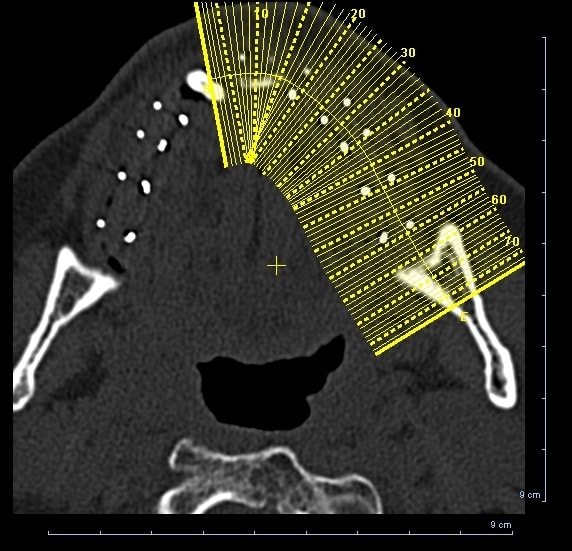

la suite du cas de 90

pour32/42 ce sont des D2 et non pas des P pano "photographies" de mauvaise qualité

à l'époque tous ça c'etait sans scanner, et c'est vrai que les axes sont...bizarre (c'est le patient qui etait tordu sans doutes

Un nouveau cas à étudier, merci du cadeau Béotien

Des avis?

Si on fait une expansion, cette serra chez toi

sur un opt , c'est pas top pour voir quoi faire.

un ptit scan ?